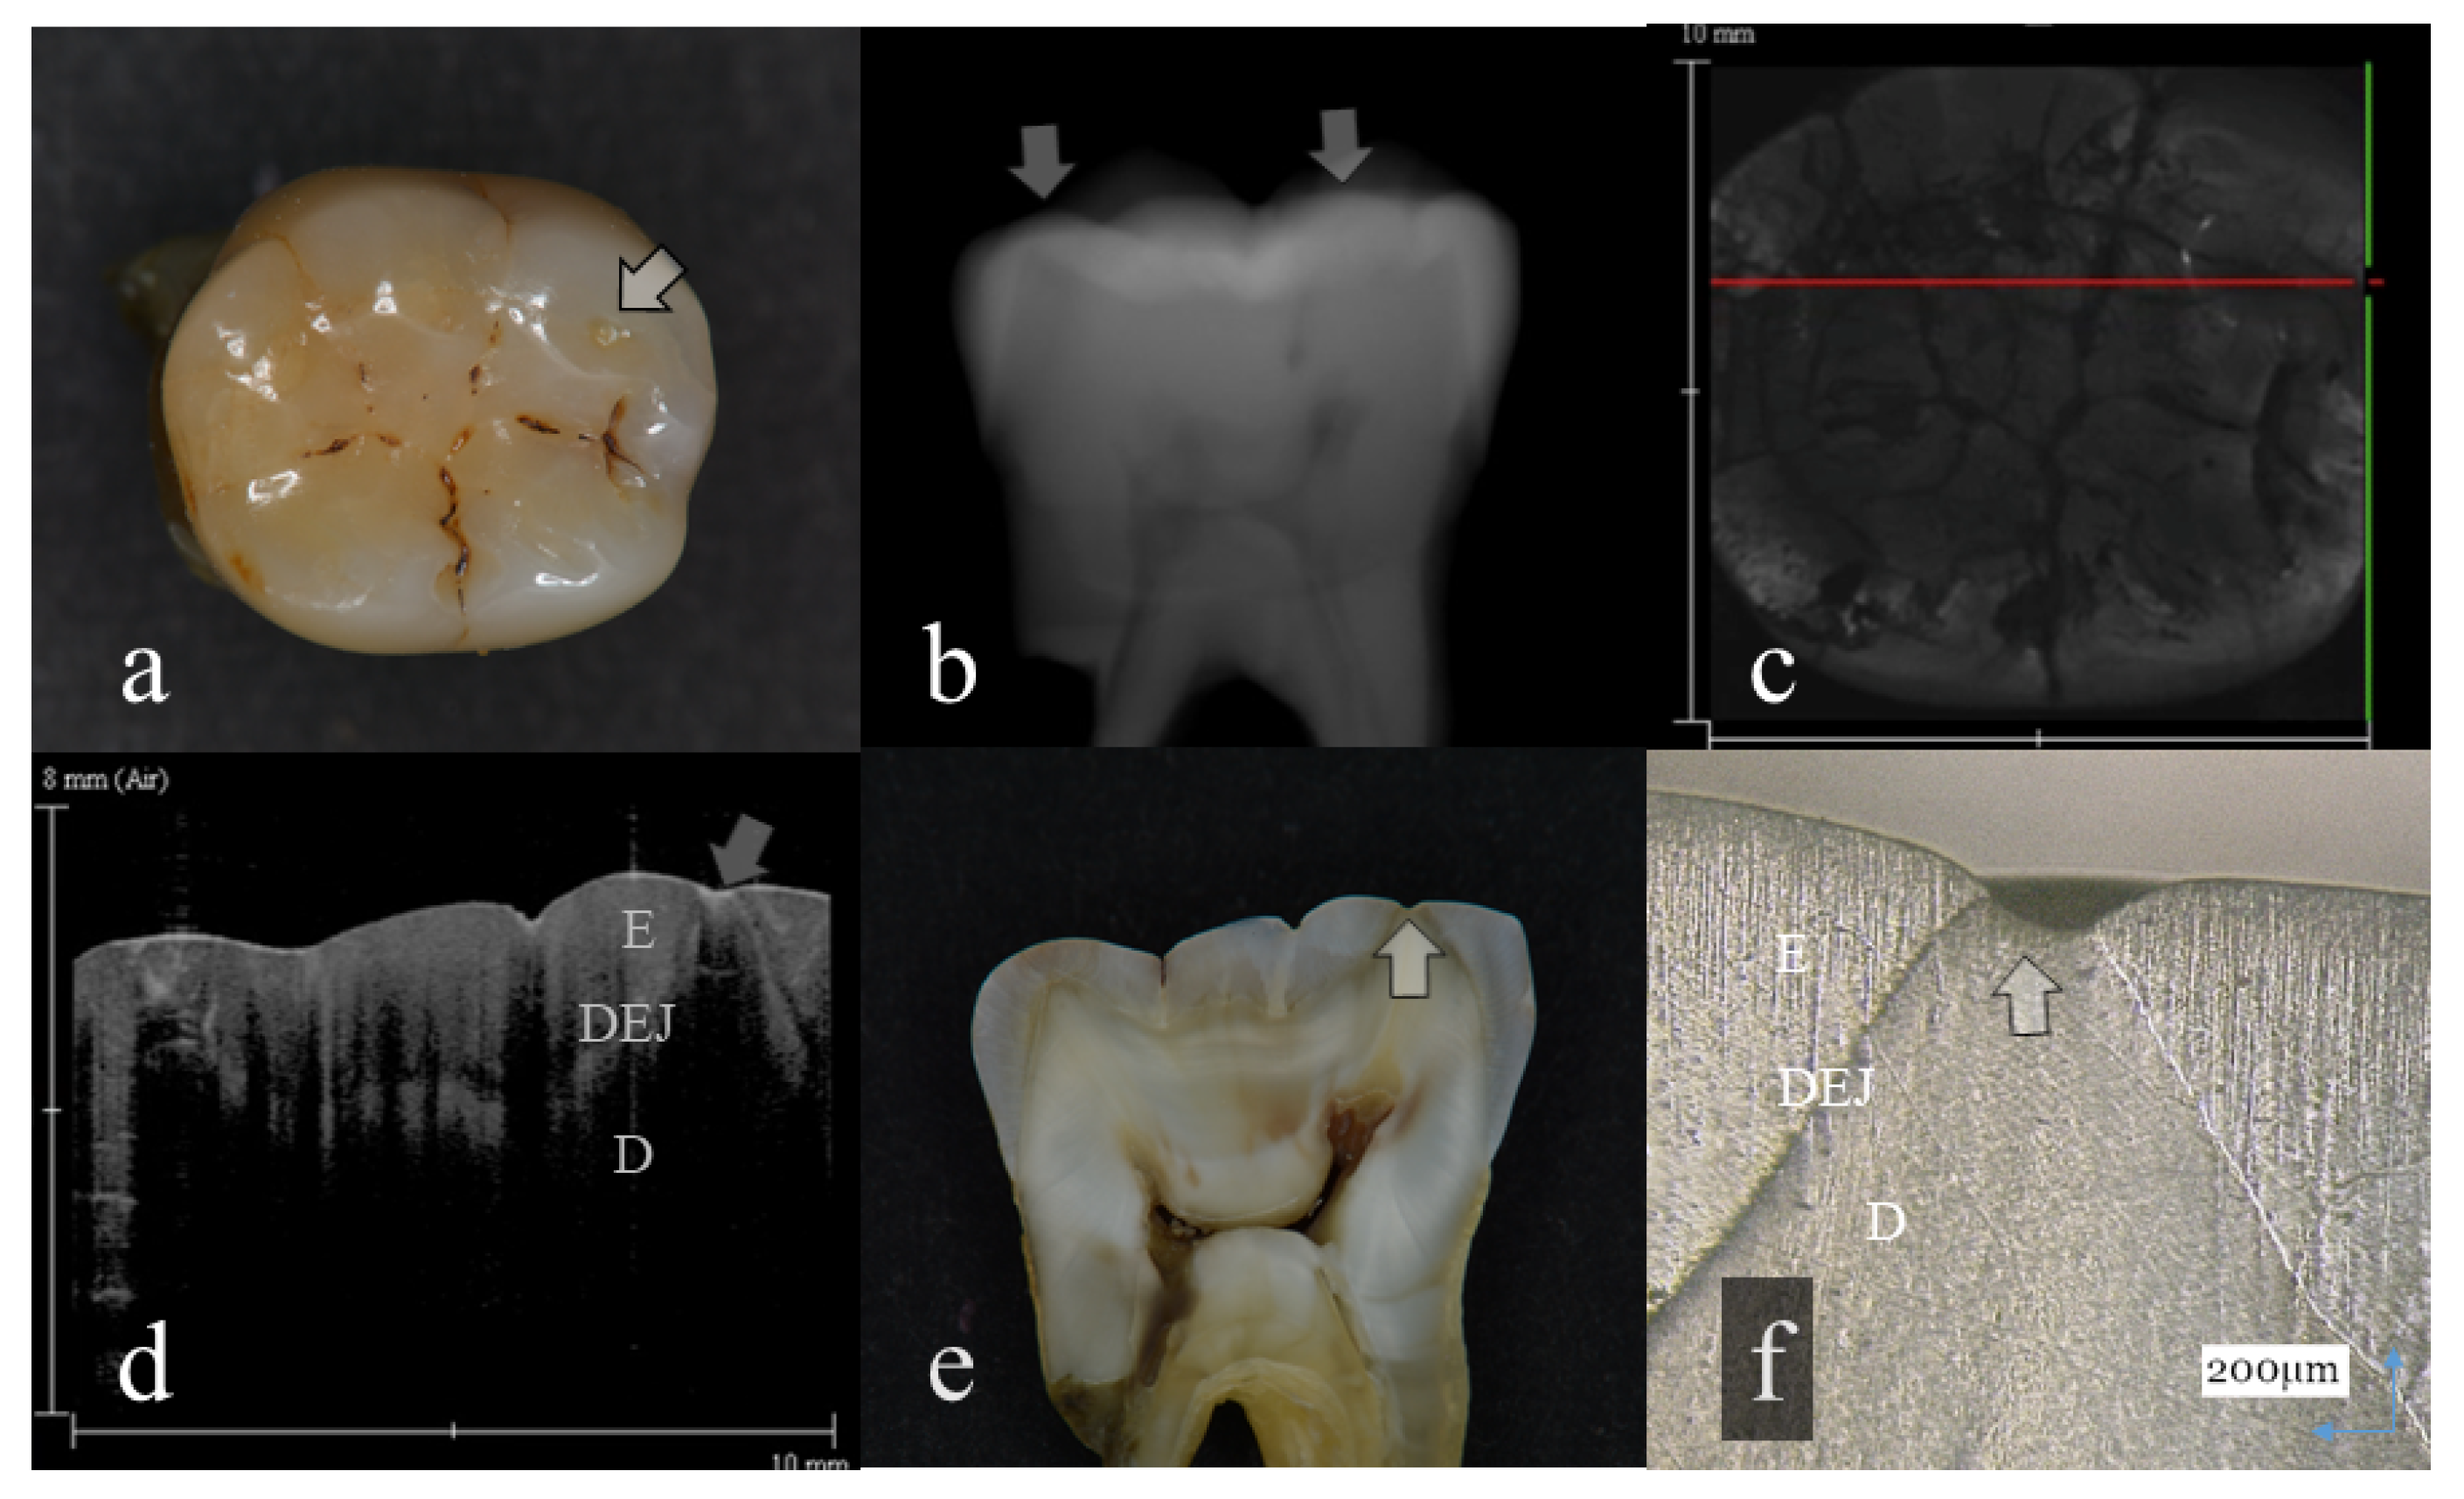

Figure 2.

Distinct enamel wear without dentin exposure (score 2): (a): Occlusal view. The surface of mesial lingual cusp appeared slightly collapsed (arrow); (b): Digital intraoral radiography. Occlusal surface of mesial cusp appeared flattened (arrow); (c): OCT en face intensity projection; (d): SS-OCT image. Occlusal enamel remaining on the lingual cusp was extremely thin because of the tooth wear. However, dentin was not involved at the tooth wear (arrow); (e): Histological view. Remaining enamel at the lingual cusp was extremely thin (arrow); (f): CLSM image of histological view. Remaining enamel was observed on the lingual cusp dentin (arrow). The corresponding dynamic slicing 3D video is in Supplementary Materials: Video S2. The image on the upper right is a cross sectional view. Lower right is an en face view.

In OCT, amount of enamel loss could be estimated by the cross-sectional view of remaining enamel thickness, as the DEJ was clearly visualized as a landmark in all the OCT scans (Figure 1 and Figure 2). Since intact enamel allows the OCT signal to penetrate deep with less scattering, the whole thickness of occlusal enamel could be monitored in this study, resulting in the higher agreement with histological findings (Table 3). These results correlate well with previous study findings measuring the remaining enamel thickness of tooth wear surfaces using cross-polarization (CP) OCT [25,26]. The CP-OCT measurement of remaining enamel thickness was reported to show excellent agreement with the μ-CT measurement [25,26]. Meanwhile, as the enamel thickness is highly location dependent, 3D OCT could visualize the remaining enamel thickness for the area of scanned tooth surface to find the position with the remaining enamel becoming thinner, without the need for additional scanning (Videos S1 and S2). Consequently, dentists allow finding of the location where therapeutic management is necessary, even for patients at the asymptomatic stage. In radiography, level of enamel wear is difficult to see because of the superimposition of dense buccal and lingual cusps, and visual inspection from the occlusal view estimating the topographical and color changes appears more informative in many cases.